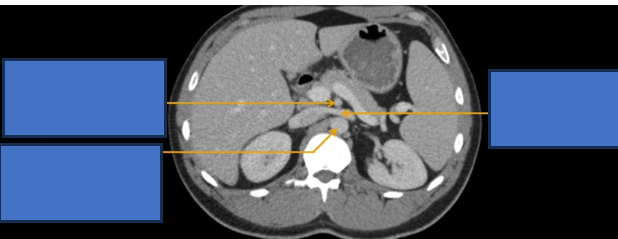

đm thận T?